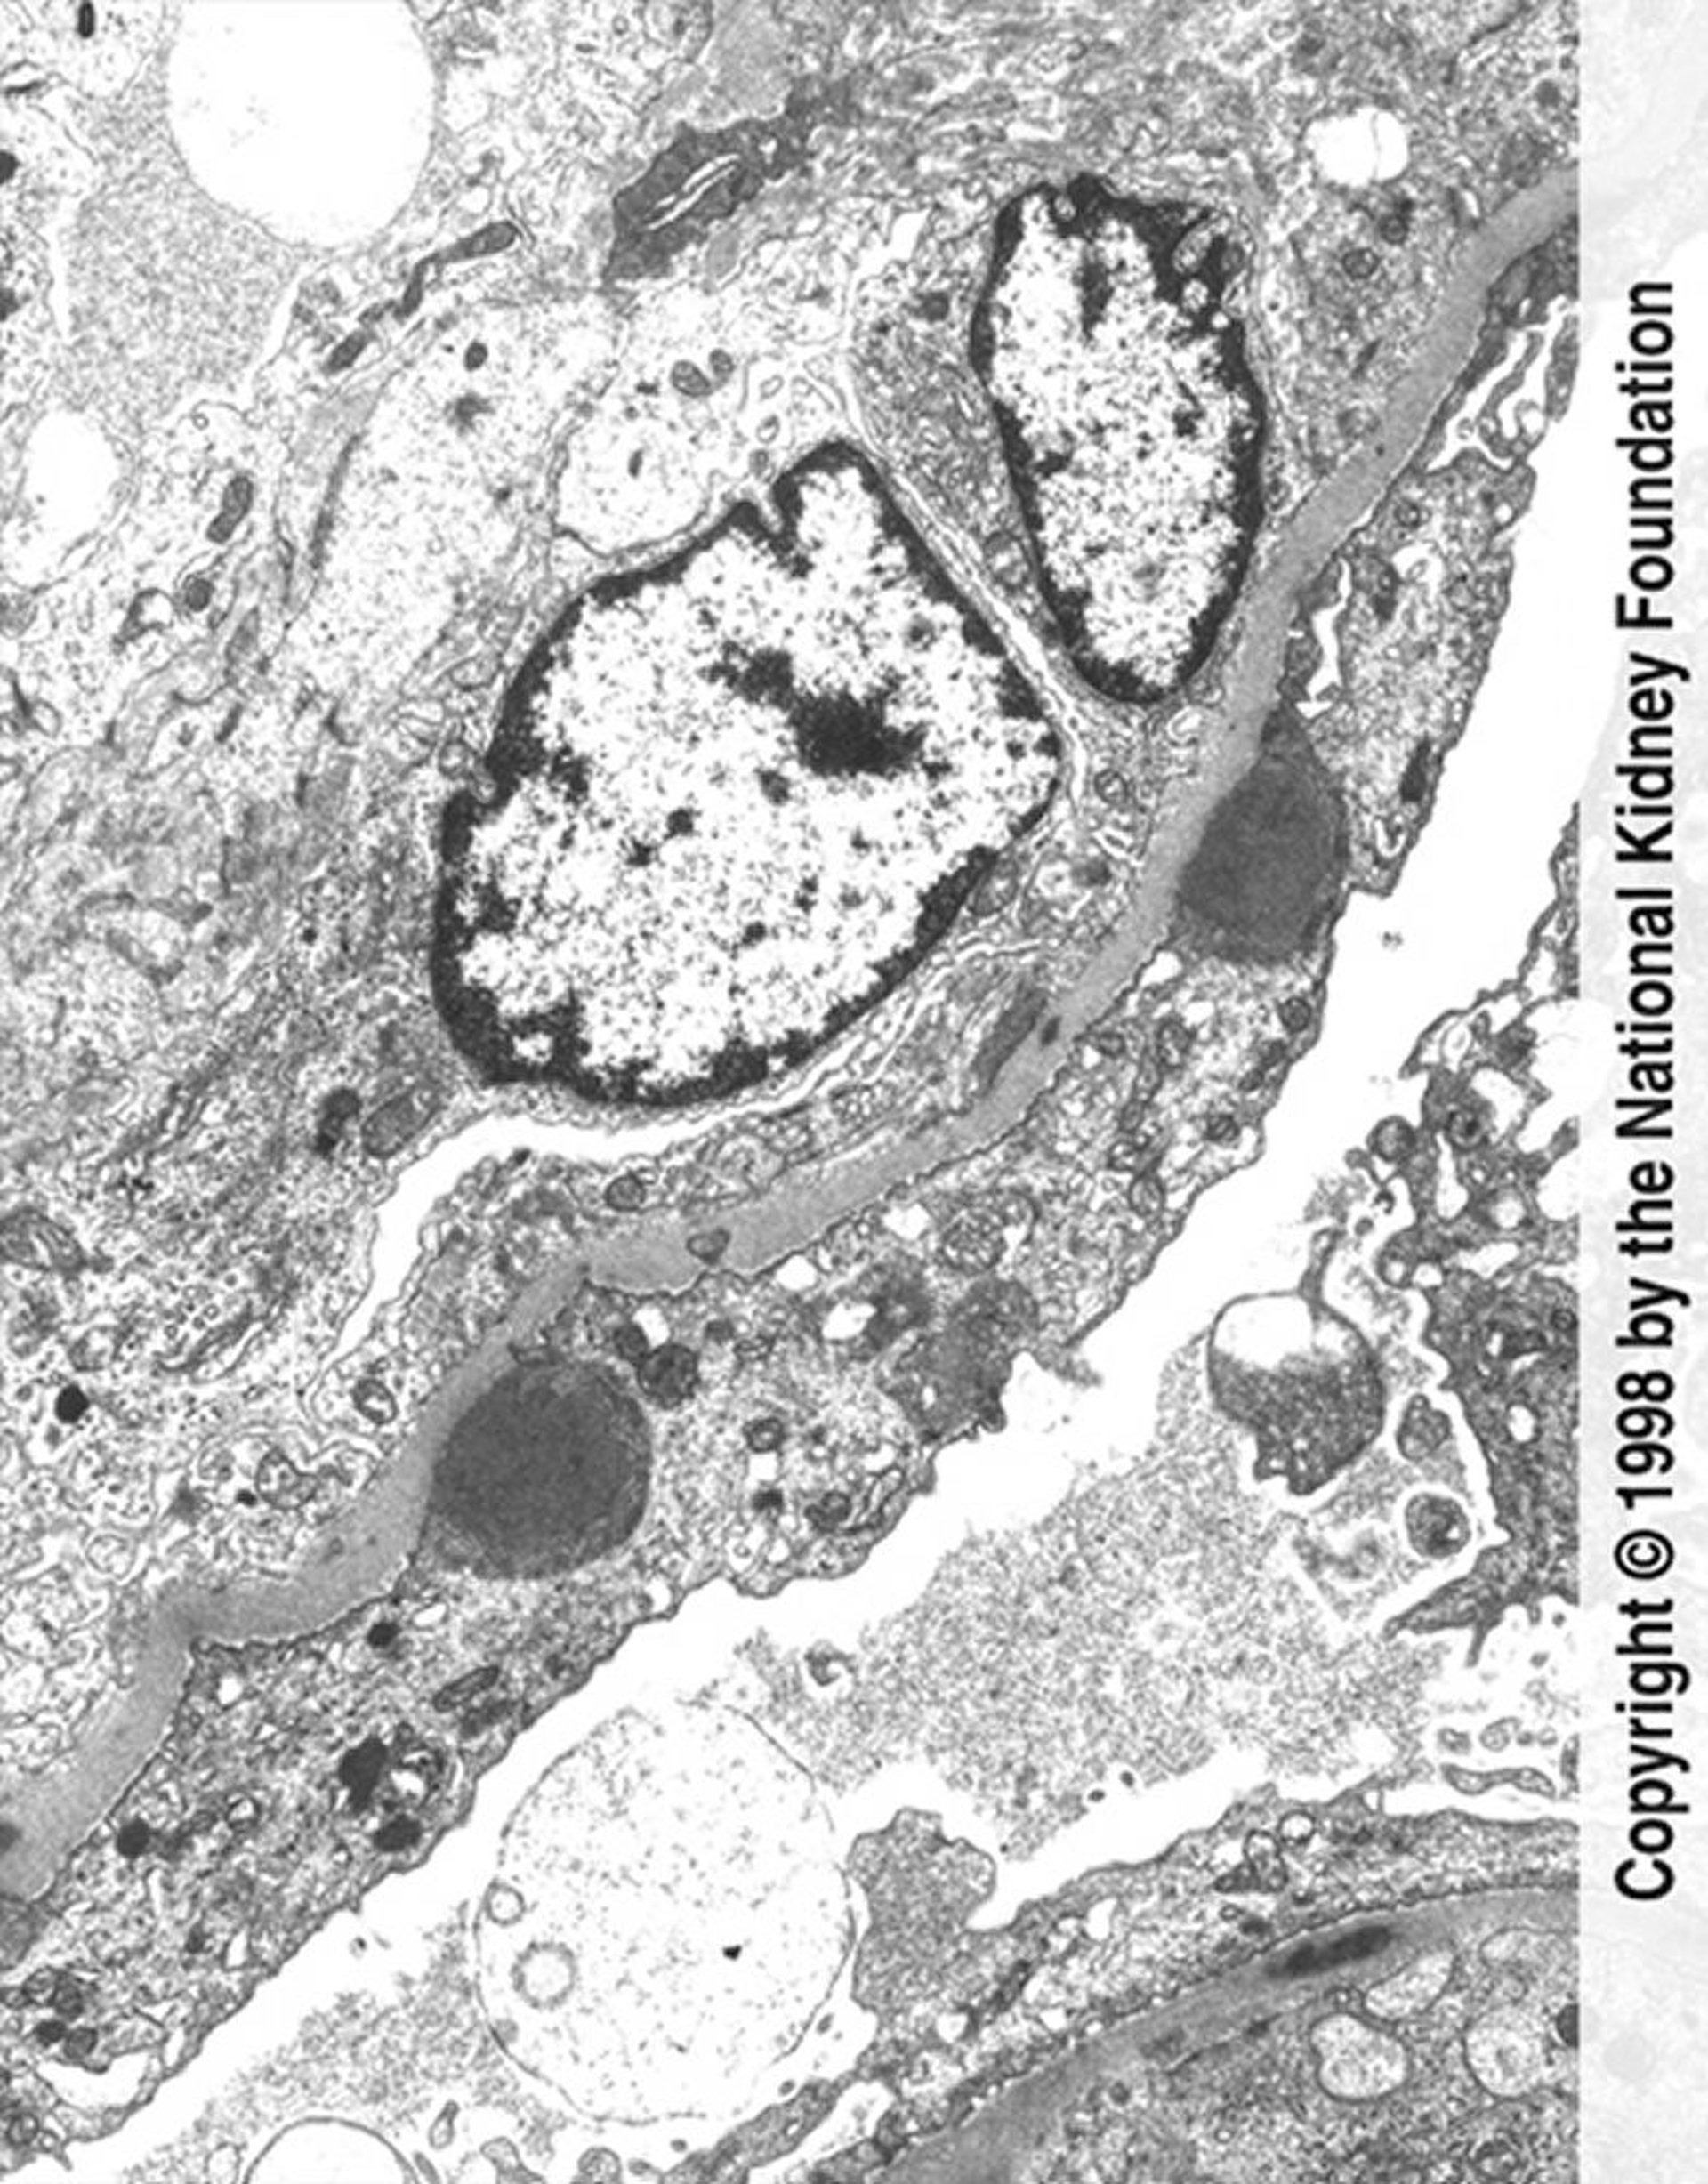

Постінфекційний гломерулонефрит (відкладення імунного комплексу)

Hump-shaped immune complex deposits (dark gray) with extensive foot process effacement and endocapillary proliferation are seen on transmission electron micrograph (×11,250).

Image provided by Agnes Fogo, MD, and the American Journal of Kidney Diseases' Atlas of Renal Pathology (see www.ajkd.org).